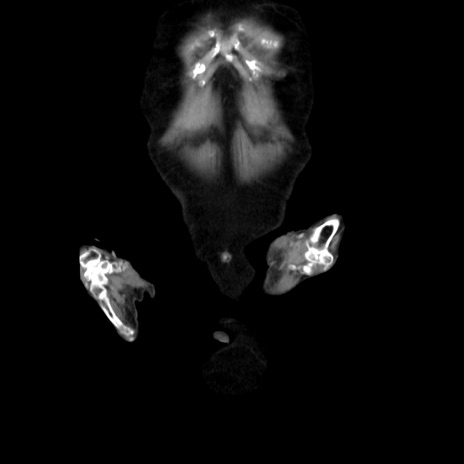

症例40(冠状断像)

冠状断像